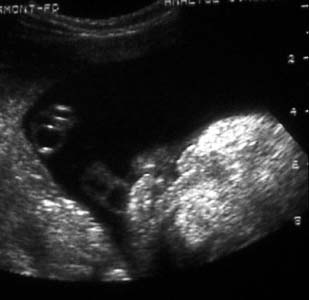

Atteinte associée du palais